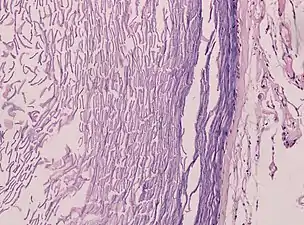

Histopathology, showing a keratinizing stratified squamous epithelium, and a lumen containing keratin flakes

Histopathology showing epithelium and lamellated keratin (left)